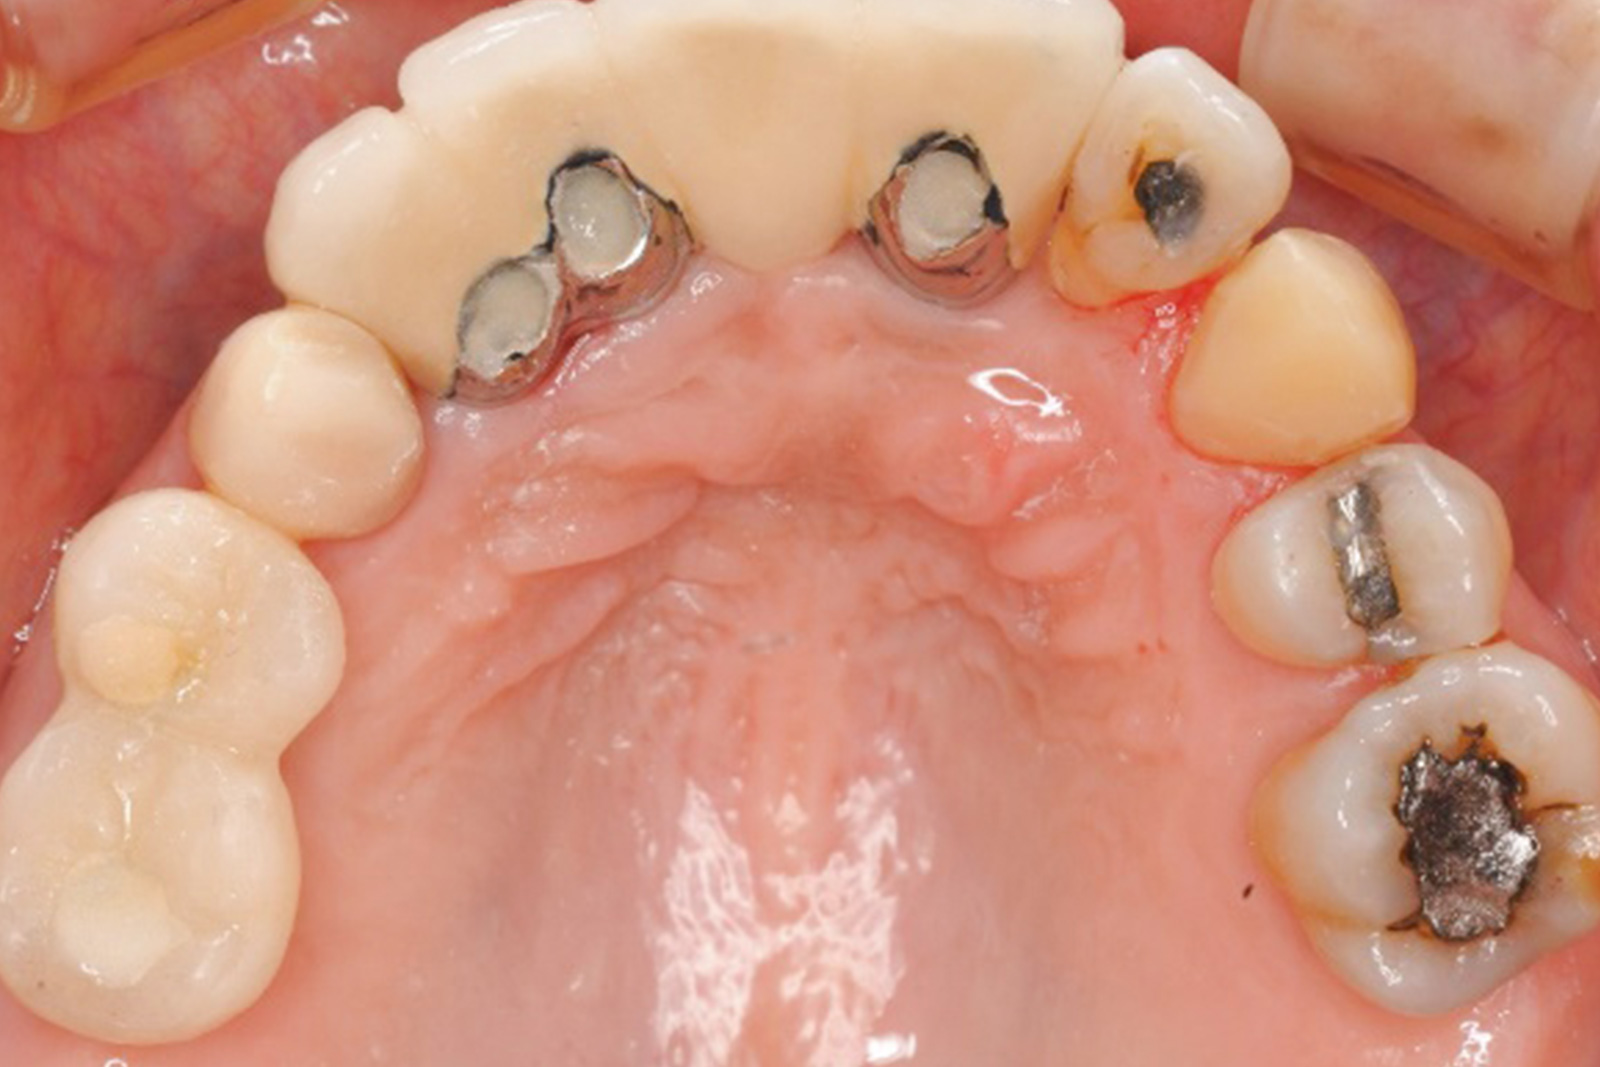

当院がこれまで、どのような症例を手がけてきたのか。その一例を紹介します。

歯や歯茎、歯を支える顎の骨までも含めた口の中全体を整える治療は非常に難しく、緻密な治療計画と確かな技術が求められます。

歯がボロボロになり崩壊した口の中を改善し、見た目も整えるために、当院では歯科の各分野の専門家がチームを組み、さまざまな手法を使って治療を進めます。

患者さんに納得いただける治療を実現するため、当院では各分野の専門家が密接に連携する「チーム医療」を推進しています。それは「高度な治療を適切に提供するには1人の医師の力では限界がある」と考えているからです。

チーム医療とは、治療の工程を細分化し、それぞれの工程で別々の専門家が治療にあたるスタイルです。